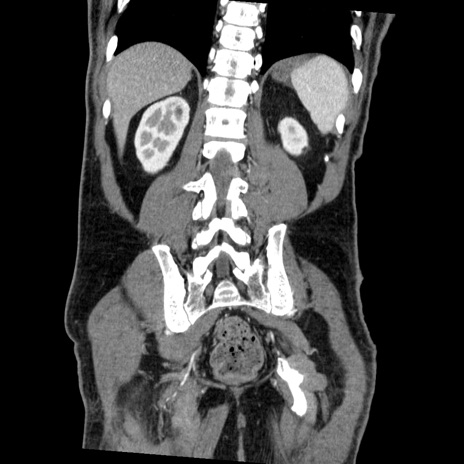

症例22(冠状断像)

【症例】50歳代男性

【主訴】腹痛

【現病歴】AVMからの被殻出血のため回復期リハ病棟入院中。 本日午後3時頃急に下腹部痛が出現した。

【既往歴】AVM、被殻出血、虫垂炎、高血圧

【身体所見】意識晴明、左半身不全麻痺、会話の理解は良好、36.5°C、腹部:膨隆、全体に板状硬、下腹部正中に圧痛点あり、反跳痛-、筋性防御不明、右下腹部にope scar

【データ】WBC 9400、CRP 0.06